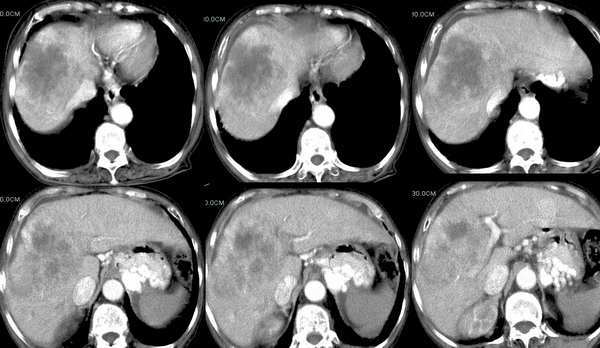

延时期10分钟及12分钟

可以肯定为肝癌;首先要指出的是,这个病例的三期扫描不规范,动脉期时间太早了,而门脉期的表现却是动脉期的表现,肾脏皮髓质交界清晰,说明处在动脉期但又略晚了点,看肝癌表现,以动脉晚期最为可靠,即动脉显影明显,脾脏呈花斑样强化,门脉初步显影,此表现为诊断肝癌最可靠的时期。这个病例肝脏有硬化表现,合并腹水,增强后病灶明显强化且边界不清,肝动脉异常增粗,门脉右支受侵,右后叶也有一处小病灶,为子灶。我的诊断为:肝右叶原发浸润型肝癌,肝硬化,门脉高压,腹水。下肢浮肿,可能为下腔静脉癌栓形成。

支持影像王分析,考虑肝右叶原发浸润型肝癌(巨块型),肝硬化,门脉高压,腹水。

支持影像王分析,考虑肝右叶原发浸润型肝癌(巨块型)伴门静脉右前支受侵,肝硬化,门脉高压,腹水。ivc有无受累单从片内表现依据不足。